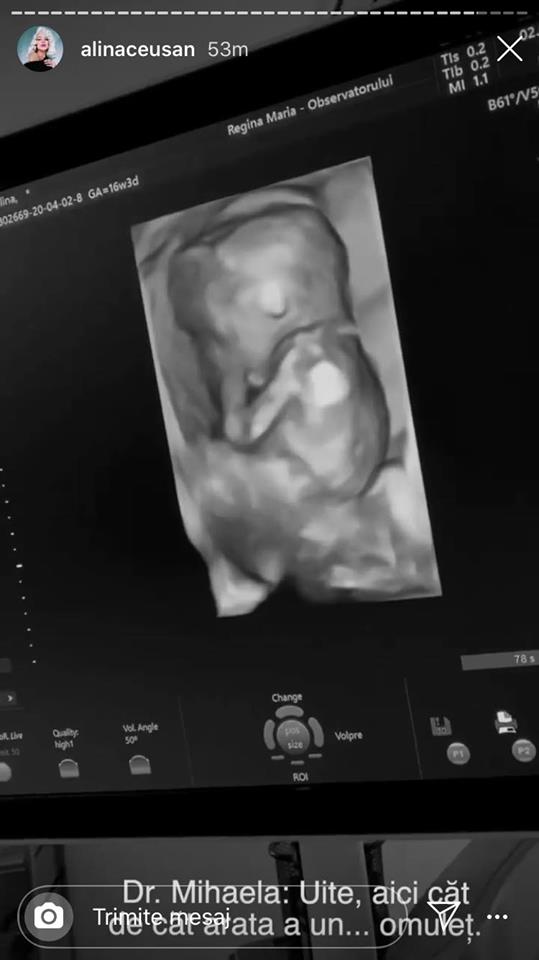

Alina Ceușan este însărcinată în șase luni și a dat vestea cea mare printr-un video superb pe care l-a postat pe Instagram. Vloggerița a surpins în imagini primele ei zile din viața de gravidă alături de soțul ei, dar și primele imagini cu bebelușul.